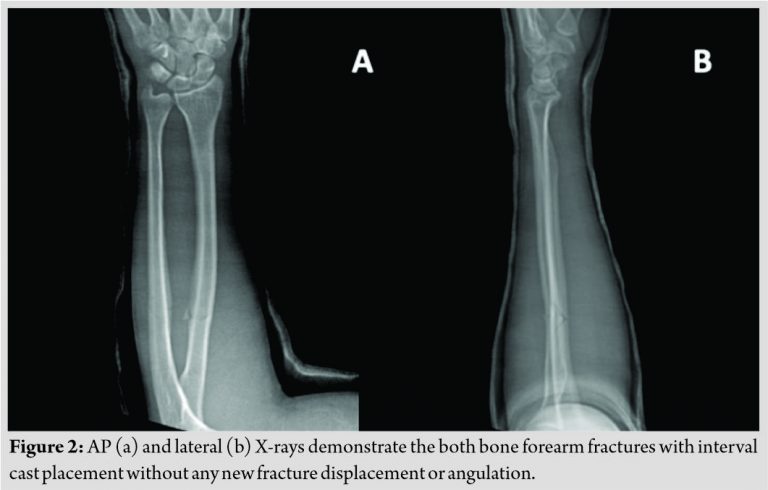

A 23-year-old, Caucasian, right hand dominant male, otherwise healthy, was seen in the emergency department after a skateboard accident. He reported falling onto his dorsal left proximal forearm and experienced immediate pain in the area without other injuries. Physical examination was notable for tenderness over the proximal radius and ulna and limited pronosupination secondary to pain. Plain radiographs demonstrated non-displaced but slightly comminuted, short oblique fractures of the proximal third of the radius and ulna (Fig. 1a, b). After discussion with the patient and his family, the decision was made to place the patient in a long arm cast (Fig. 2a, b) and follow-up in the clinic in 1 week.